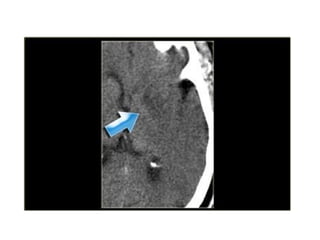

4.Dense MCA sign

• This is a result of thrombus or embolus in

the MCA.